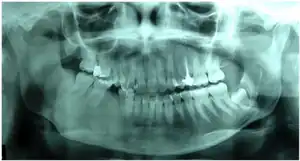

| Panoramic X-ray (2013) showing radioopaque area of the image with the appearance of ground glass in the right hemimandible. Recurrence of the lesion. | |